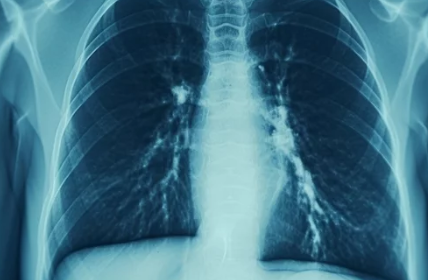

- 영상 검사: 흉부 X-ray를 통해 폐에 염증이 있는지 확인합니다.